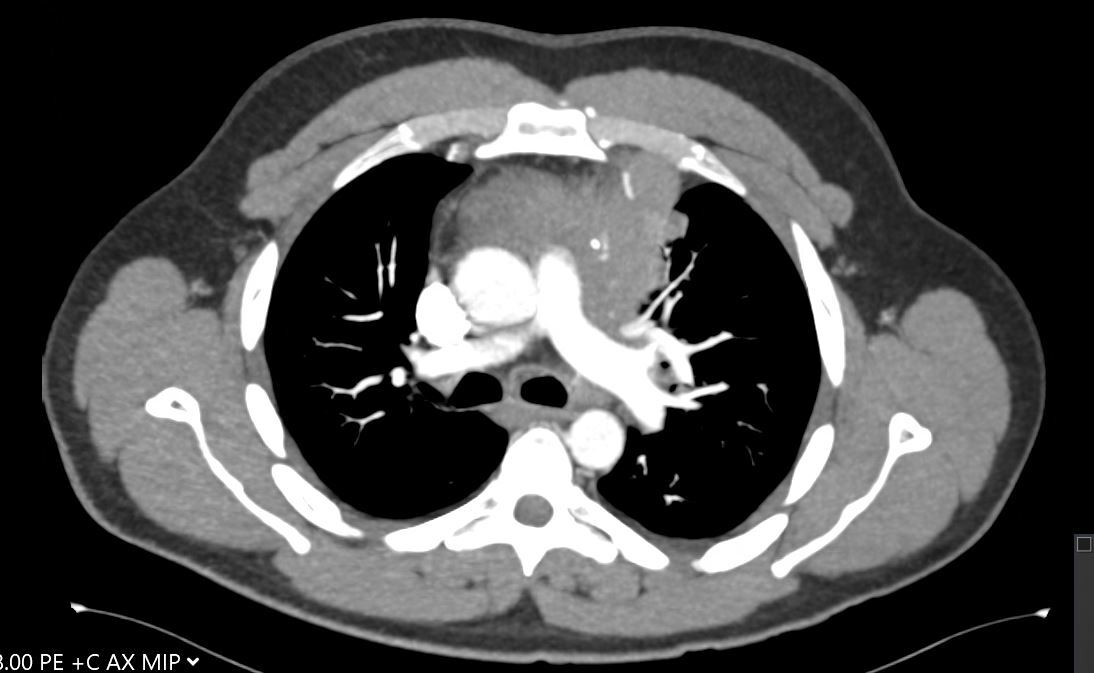

A 30-year-old man presents with dyspnea and is found to have an anterior mediastinal mass, as well as supraclavicular lymphadenopathy; biopsy of the mass is consistent with thymic carcinoma. Imaging shows his anterior mediastinal mass, lung and diaphragmatic lesions consistent with metastatic malignancy, and probable pericardial involvement with small pericardial effusion (Figures 1, 2, 3, and 4).

Fig. 1: CT image showing large mediastinal mass found to be thymic carcinoma. -

Fig. 2: CT image showing large mediastinal mass found to be thymic carcinoma. -